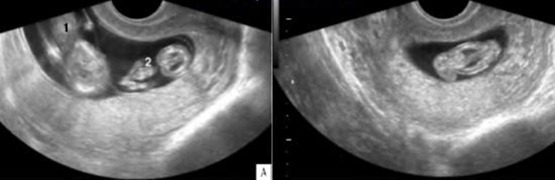

После выполнения УЗИ до 10 недели беременности врач определяет эмбрионы, подлежащие редукции, осуществляет их картирование в полости матки. Затем выставляют показания к способу проведения процедуры – трансвагинальному или трансабдоминальному. Трансцервикальный не применяется в настоящее время из-за своей травматичности.

Трансвагинальный способ редукции допустим на сроке до 8 недель, поскольку менее травматичен именно в этот период. Трансабдоминальный – более эффективен на поздних сроках до 13 недель.

Под внутривенным наркозом в асептических условиях под контролем УЗИ осуществляют доступ – прокол специальным пункционным адаптером-катетером. Он направляется к амниотической оболочке эмбриона. Затем через катетер проводится более тонкая игла, прокалывающая грудную полость, вводится раствор калия хлорида – сердцебиение плода прекращается.

В полной остановке сердечной деятельности редуцируемого эмбриона можно убедиться после 5-10 минут УЗИ-контроля.